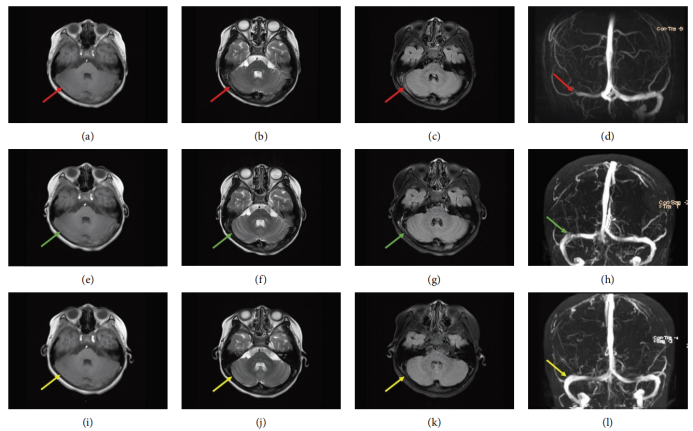

· 诊断性MRI/MRV:入院后进行的MRI/MRV检查明确显示了右侧横窦、乙状窦及颈内静脉颅内段的血栓形成,表现为T1WI呈混杂信号,T2WI及FLAIR序列呈高信号,MRV上相应区域出现血流信号中断(充盈缺损)。

· 疗效评估:治疗过程中的动态影像学变化证实了抗凝治疗的有效性。

3:治疗前后影像学疗效评估

时间点

影像学检查

主要发现

结论

治疗前

MRI/MRV

右侧横窦、乙状窦及颈内静脉颅内段血栓形成,血流信号中断。

明确诊断

治疗后7天

MRV

右侧横窦、乙状窦血栓负荷显著减少,可见部分血流信号恢复。

治疗有效

治疗后3个月

右侧横窦、乙状窦及颈内静脉颅内段血栓完全消失,静脉窦完全再通,血流信号恢复正常。

血栓完全溶解